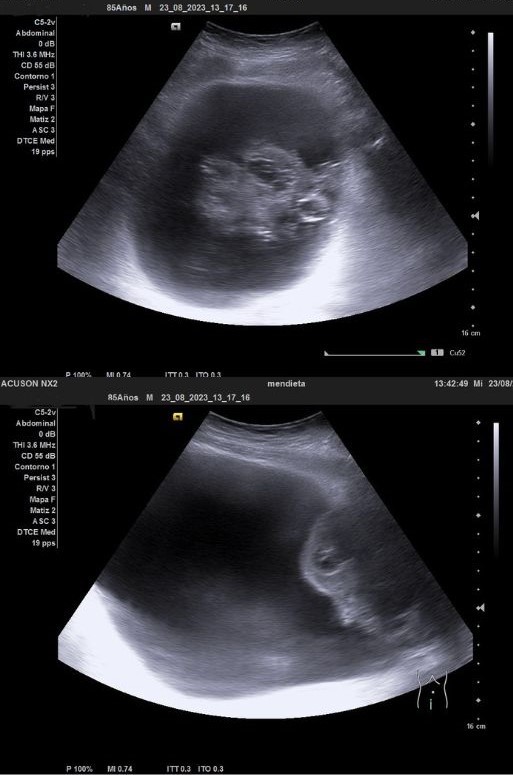

Ecografía clínica urológica: se objetiva vejiga muy distendida hasta epigastrio con imagen heterogénea en pared posterior de vejiga de gran tamaño que capta al Doppler color sospechosa de malignidad. Con signo de hidronefrosis riñón izquierdo grado III.